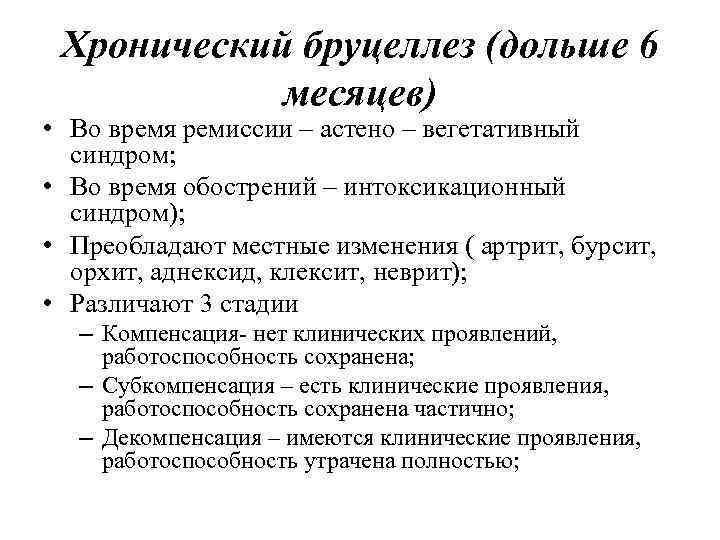

Хронический бруцеллез (дольше 6 месяцев) • Во время ремиссии – астено – вегетативный синдром; • Во время обострений – интоксикационный синдром); • Преобладают местные изменения ( артрит, бурсит, орхит, аднексид, клексит, неврит); • Различают 3 стадии – Компенсация- нет клинических проявлений, работоспособность сохранена; – Субкомпенсация – есть клинические проявления, работоспособность сохранена частично; – Декомпенсация – имеются клинические проявления, работоспособность утрачена полностью;

Хронический бруцеллез (дольше 6 месяцев) • Во время ремиссии – астено – вегетативный синдром; • Во время обострений – интоксикационный синдром); • Преобладают местные изменения ( артрит, бурсит, орхит, аднексид, клексит, неврит); • Различают 3 стадии – Компенсация- нет клинических проявлений, работоспособность сохранена; – Субкомпенсация – есть клинические проявления, работоспособность сохранена частично; – Декомпенсация – имеются клинические проявления, работоспособность утрачена полностью;